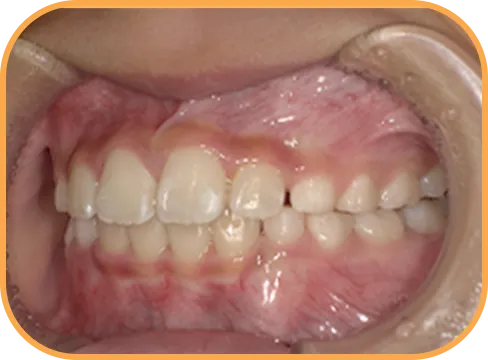

• Before

• 正 面

治療前正面からの歯の様子

• 上 顎

治療前上顎からの歯の様子

• 下 顎

治療前下顎からの歯の様子

• 右 側

治療前右側からの歯の様子

• 左 側

治療前左側からの歯の様子

主 訴

前歯ガタガタ、前歯が大きい

治療内容

インビザライン・ファースト

治療期間

7か月

治療費(税別)

450,000円+診断料5,000円

リスク・副作用

• 親知らずの影響や加齢などによって、凸凹が生じる可能性があります。

• 治療の初期段階では痛みや不快感が生じやすくなりますが、1週間前後で慣れます。

• 顎の成長発育によって、噛み合わせや歯並びが変化する可能性があります。

• 状況により当初予定した治療計画を変更する可能性があります。